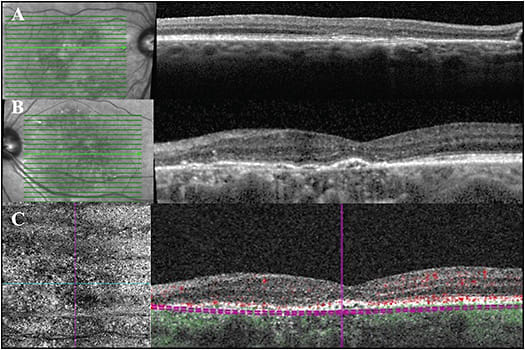

Rarely, CSCR may coexist with nonexudative AMD, and differentiating exudative AMD vs. CSCR with or without CNV may be difficult. We present here a challenging patient case in which OCT and OCT-A were able to identify a patient with intermediate AMD of the right eye and CSCR with indolent secondary Type 1 neovascularization of the left eye super-imposed on intermediate AMD.

Clinical fundus exam demonstrated intermediate drusen of both eyes with pigment changes in the left eye and no hemorrhage. Figures 4A, 4B highlight the foveal cross-sectional OCTs of the right and left eye, respectively. The right eye demonstrates small drusenoid PEDs. This is notably overlying a thickened choroid with enlarged or pachyvessels. The left eye demonstrates SRF in excess to what would be expected for exudative AMD. There is also a confluent row of PEDS forming a double-layer sign.

OCT-A (Figure 4C) of the left eye, segmented at the level of the choriocapillaris, demonstrates Type 1 neovascularization at the nasal side of the PED. Note, cross-sectional flow overlay signals help to localize this to the sub-RPE space. The SRF has waxed and waned over 2 years, while maintaining stable vision of 20/50. Figure 4D demonstrates a spontaneous reduction in the amount of SRF.

The patient has only received two anti-VEGF therapies over 2 years. Certainly, imaging in this case dramatically altered his injection burden and understanding of his disease. ◆